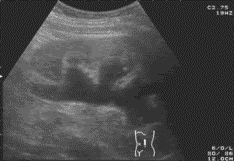

• диагностика гидронефрозаУльтразвуковое исследование (УЗИ) позволяет определить размер почки, выявить расширение чашечно-лоханочной системы, измерить толщину паренхимы.